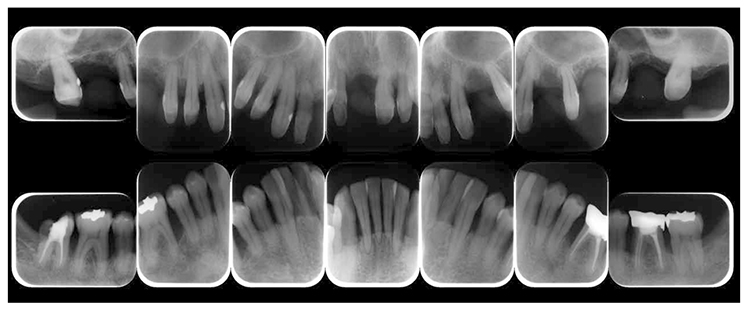

(3) X-ray findings

At the first visit, the findings showed moderate to advanced horizontal alveolar bone resorption in the entire jaw, and advanced vertical bone resorption on 24,36,46, 47. Additionally, on 46,47 were radiolucent findings that were likely associated with furcation involvement, and radiolucent areas on the alveolar bone surrounding the root apex were shown on 16,11,26. Furthermore, distally on 47, radiolucent findings showed caries extending into the dental pulp.(Fig.1c).

(Fig.1c) Dental X-ray 14 during first visit (June 2007)

2) Reevaluation testing (February 2010)

At reevaluation testing after basic periodontal treatment, the color of gingiva improved to pink, and findings showed that inflammation in the marginal gingiva with primarily blood congestion had subsided. Class 4 gingival recession (Miller’s gingival recession classification) was observed on the entire jaw. (Fig.3a). The average PD of the entire jaw was 2.8mm, maximum PD was 10.0mm, the ratio of PD of 3mm or below was 84.0%, PD of 4-6mm was 12.5%, PD of 7mm or above was 3.5% and BOP rate improved to 11.8%. However, PD of 7mm remained on 17, 10.0mm on 27, 5.0mm on 36, and 7.0mm on 46. Additionally grade 1 furcation involvement remained on the buckle and lingual side of 36, mesial distal direction on the buckle side of 17, grade 2 on the buckle side of 27. Teeth mobility was grade 1 on 44 and 46 (Fig.3b). X-ray findings showed that dental calculus was removed from the gingival margin on the maxilla and mandible. Despite the clearly visible alveolar hard line, no improvement was shown on the alveolar bone. (Fig.3c).

Fig 3c

(Fig.3c) Dental X-ray 14 after completion of basic periodontal treatment (January 2010)

7) Reevaluation testing (December 2003)

At the reevaluation examination after treatment to restore oral function, the color of gingiva was pink, and with prosthetics, intraoral harmony was replicated esthetically and functionally. (Fig.6a). The average PD across the entire jaw was 2.1mm, maximum PD was 4.0mm, the ratio of PD of 3mm or below was 99.3%, no BOP was found and the condition of the periodontal tissue was stable (Fig.6b). In the X-ray, continuity of the alveolar hard line was replicated and the sequence of bone trabeculae was normal, and therefore, the patient transitioned to the SPT phase (Fig.6c).

Fig 6c

(Fig.6c) Digital X-ray 14 after completion of restoration of oral function (April 2013)

8)SPT (December 2013 onward)

After transitioning to SPT, the patient brushed 4 times daily after every meal and before bedtime and has continued to use an interdental brush. PCR levels have been consistently in the 20% range. SPT , which primarily consists of instructions on brushing and dental surface cleaning, has been implemented every other month to present, and efforts are made to maintain and manage oral hygiene in the long term to ensure that plaque control is not insufficient. While minor discoloring is observed on the prosthetics, the color of the gingiva is salmon pink and a macroscopically healthy appearance has been sustained (Fig.7a) . The average PD on the entire jaw is 2.1mm,maximum PD is 4.0mm,the ratio of PD of 3mm or less is 99.3%. No BOP has been found and the condition of the periodontal tissue has been stable (Fig.7b). In the X-ray, continuity of the alveolar hard line has been replicated and the sequence of the bone trabeculae has been normal (Fig.7c).

Fig 7c

(Fig.7c) 15 years after first visit: dental X-ray 14 (December 2022)